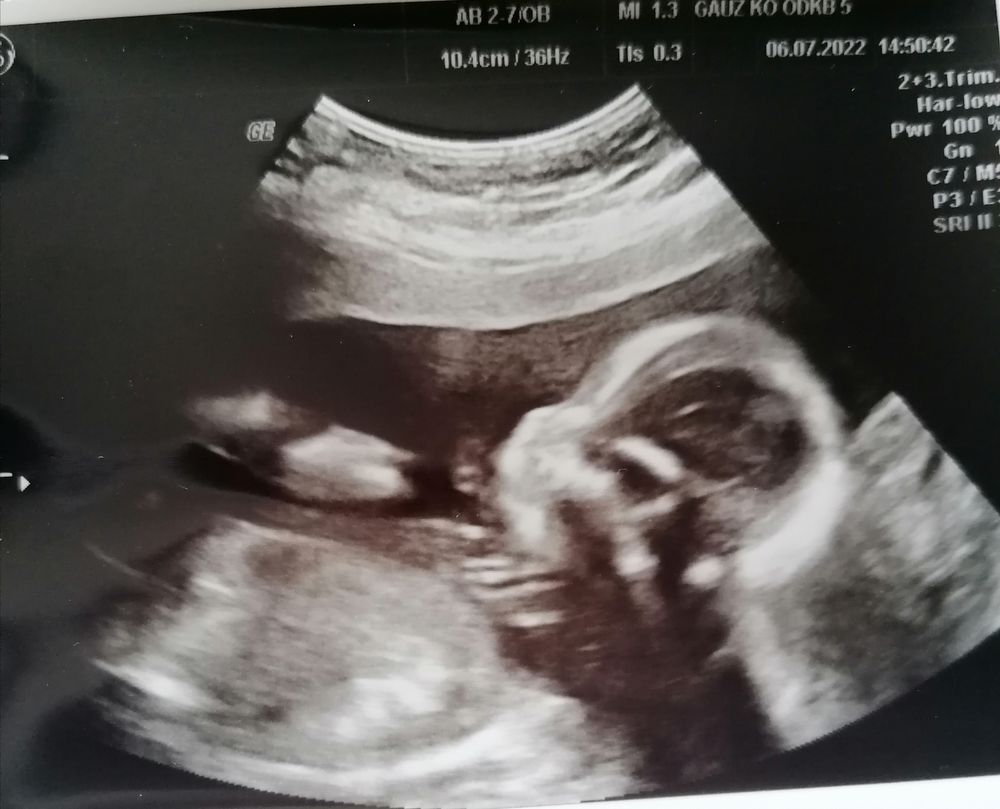

По месячным срок 18,4 недели, по 1 скринингу 19 недель по 2 скринингу поставила 18,5 недель. Все у малыша хорошо, соответствует норме, правда есть обвитие шеи пуповиной, но думаю ещё распутается.

Пока врач смотрела, несколько раз сказала, какие у ребенка огромные глазища.